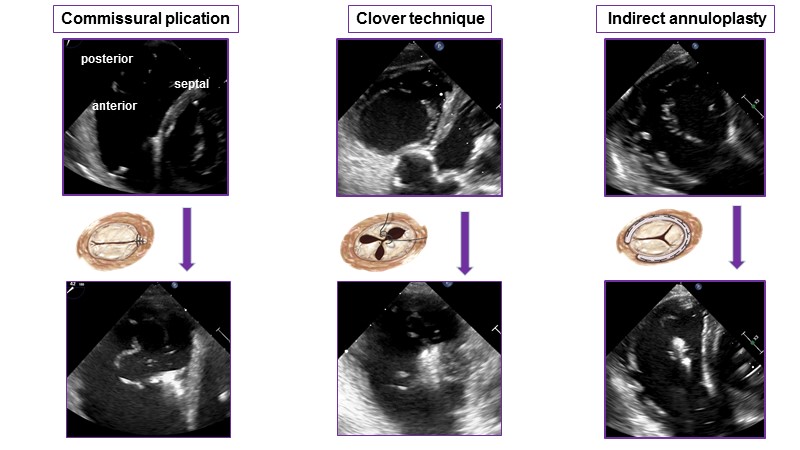

- To learn how will transcatheter therapy contribute to the treatment of tricuspid regurgitation